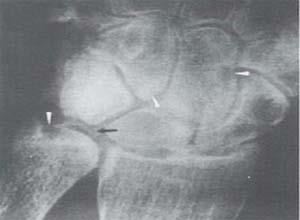

简介黏多糖贮积症Ⅴ型又称希(Scheie)氏综合征,现已被分类为黏多糖贮积症Ⅰ型的亚型,这是因为本病病人酶的缺陷与Ⅰ型相同,两者的基因与遗传方式也相同,本综合征的特征为智力正常,有中度骨骼改变、主动脉瓣病变及神经压迫症状。